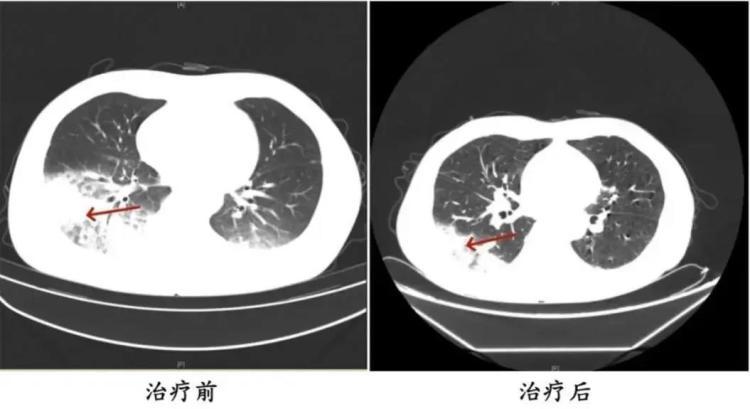

周先生治疗前后的肺部CT影像

据介绍,55岁的长沙市民周先生(化名)近日因持续发热、寒战、咳嗽4天,在医院就诊后住院接受治疗。询问病史得知,患者入院前启动了久未清洗的车载空调,每天在车上的时间超过10小时。不久后,就出现了发热、咳嗽等类似“感冒”的症状。经诊断,患者感染了军团菌肺炎。